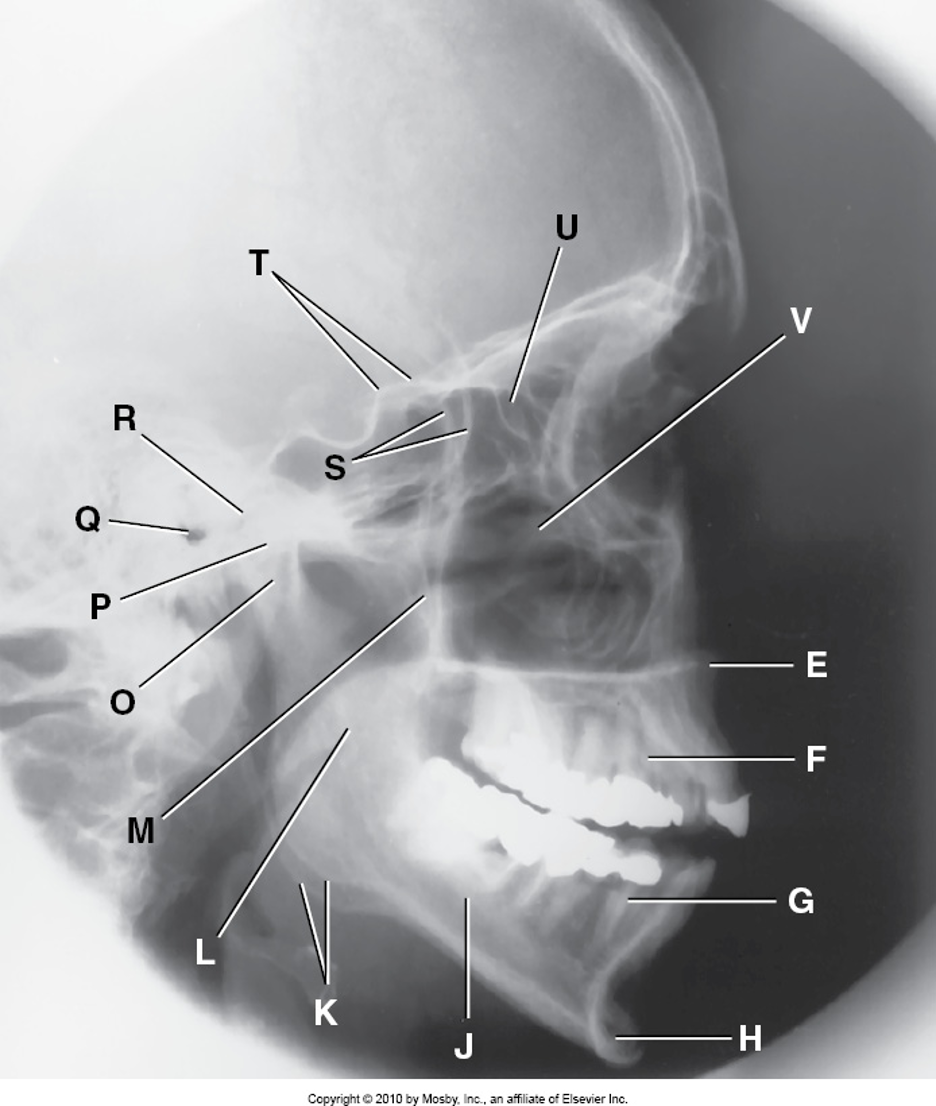

A

Zygomatic Arch

B

Right Zygomatic Bone

C

Right Nasal Bone

D

Frontal Process of Right Maxilla

E

Anterior Nasal Spine

F

Alveolar Process of Maxilla

G

Alveolar Process of Mandible

H

Mentum or Mental Protuberance

I

Mental Foramen

J

Body of Mandible

K

Angle of Mandible (Gonion)

L

Ramus of Mandible

M

Coronoid Process

N

Mandibular Notch

O

Neck of Mandibular Condyle

P

Condyle or Head of Mandible

Q

EAM

R

Temporomandibular Fossa of Temporal Bone

S

Greater Wings of Sphenoid

T

Lesser Wings of Sphenoid with Anterior Clinoid Process

U

Ethmoid Sinuses Between Orbits

V

Body of Maxilla Containing Maxillary Sinuses